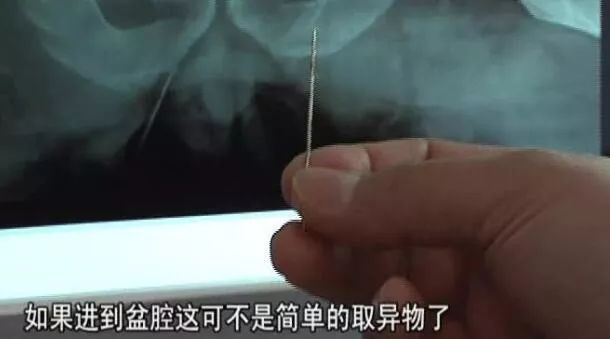

终于还是X片子火眼金睛,医生终于发现,杨先生站直了,脱裤子,再侧身摸屁股,这简单的三个动作中,进行了肌肉运动......

伴随这运动,那根神奇的绣花针,被肌肉吸得很深,运动到臀大肌的深层了,X片上看,绣花针已经紧紧贴着杨师傅的盆骨了。

必须手术!而且是大手术!

虽然这颗针已经深入到杨师傅体内,但万幸的是,针被杨师傅的骨头组织挡着,最后没有进到盆腔。

“加入这个针进到你的盆腔,这就已经不再是简单的取异物的小手术,而是开腹手术了!”